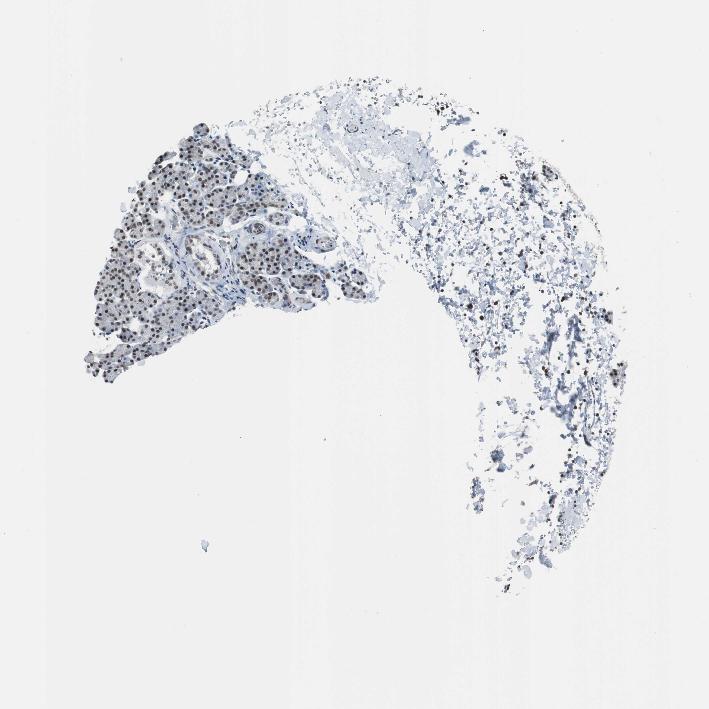

SALIVARY GLAND - Antibody stainingi

Antibody staining in the annotated cell types in the current human tissue is reported as not detected, low, medium, or high, based on conventional immunohistochemistry profiling in selected tissues. This score is based on the combination of the staining intensity and fraction of stained cells.

Each image is clickable and will lead to virtual microscopy that enables deeper exploration of all samples and also displays staining intensity scores, fraction scores and subcellular localization as well as patient and tissue information for each sample.

Antibody HPA006429

Glandular cells Medium